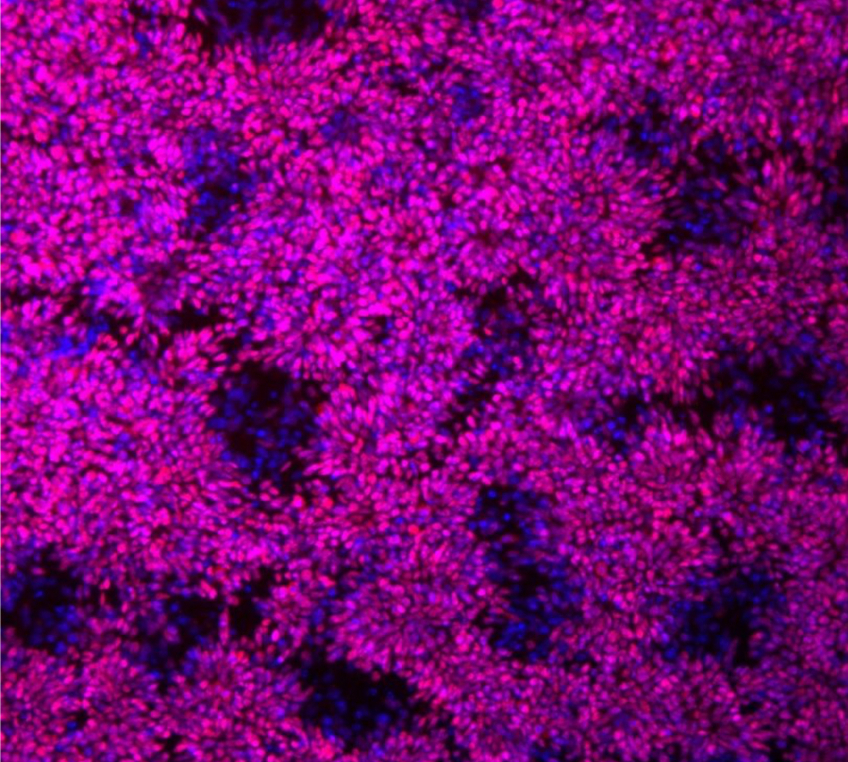

خلايا جذعية عصبية من الشمبانزي

تشير النتائج الجديدة إلى أنه يبدو أن الاختلافات تكمن خارج الجينات التي ترمز / تشفر البروتينات فيما وُسم ب ”DNA عديم الفائدة junk DNA“، والذي كان يُعتقد أن لا وظيفة له ويشكل غالبية حمضنا النووي.